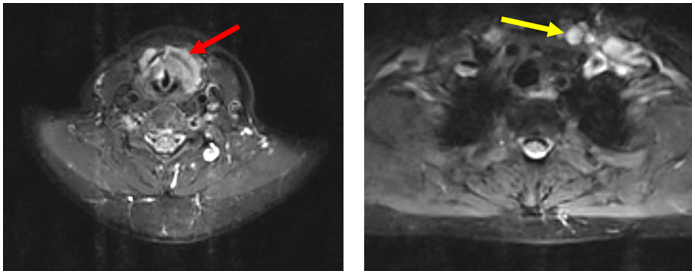

-         MRI vùng cổ (T1/2025)

Hình 1: Khối xâm lấn vùng hạ họng – thanh quản kích thước 41 x 22 mm (mũi tên đỏ), hạch cổ 2 bên, hạch lớn nhất đường kính 10 mm (mũi tên vàng).